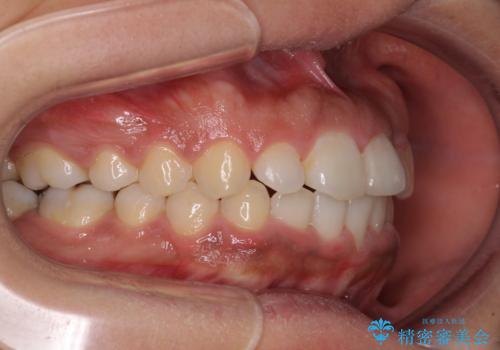

- 上下前歯の叢生を気にして来院された患者様です。

2年ほどインビザライン矯正を続けましたが、終了することができず、ワイヤーへ転換後は1年弱で終えることができました。